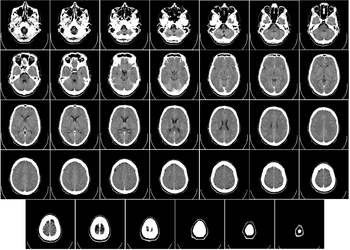

Head

CT scanning of the head is typically used to detect infarction, tumors, calcifications, haemorrhage and bone trauma. Of the above, hypodense (dark) structures can indicate edema and infarction, hyperdense (bright) structures indicate calcifications and haemorrhage and bone trauma can be seen as disjunction in bone windows. Tumors can be detected by the swelling and anatomical distortion they cause, or by surrounding edema. Ambulances equipped with small bore multi-sliced CT scanners respond to cases involving stroke or head trauma. CT scanning of the head is also used in CT-guided stereotactic surgery and radiosurgery for treatment of intracranial tumors, arteriovenous malformations and other surgically treatable conditions using a device known as the N-localizer.[12][13][14][15][16][17]

Two-dimensional CT images are conventionally rendered so that the view is as though looking up at it from the patient's feet.[57] Hence, the left side of the image is to the patient's right and vice versa, while anterior in the image also is the patient's anterior and vice versa. This left-right interchange corresponds to the view that physicians generally have in reality when positioned in front of patients.

CT data sets have a very high dynamic range which must be reduced for display or printing. This is typically done via a process of "windowing", which maps a range (the "window") of pixel values to a greyscale ramp. For example, CT images of the brain are commonly viewed with a window extending from 0 HU to 80 HU. Pixel values of 0 and lower, are displayed as black; values of 80 and higher are displayed as white; values within the window are displayed as a grey intensity proportional to position within the window. The window used for display must be matched to the X-ray density of the object of interest, in order to optimize the visible detail.